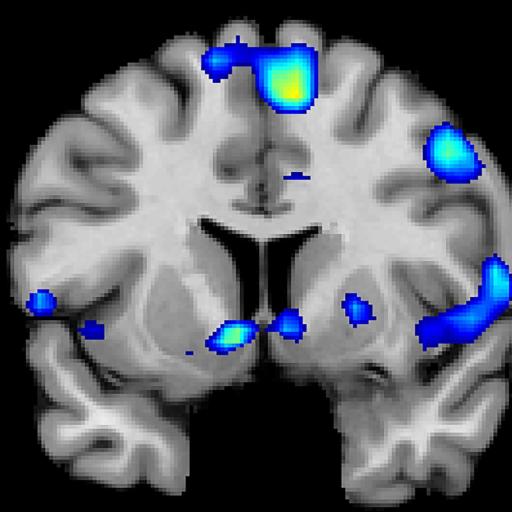

Researchers scan the brains of people having strong spiritual experiences.